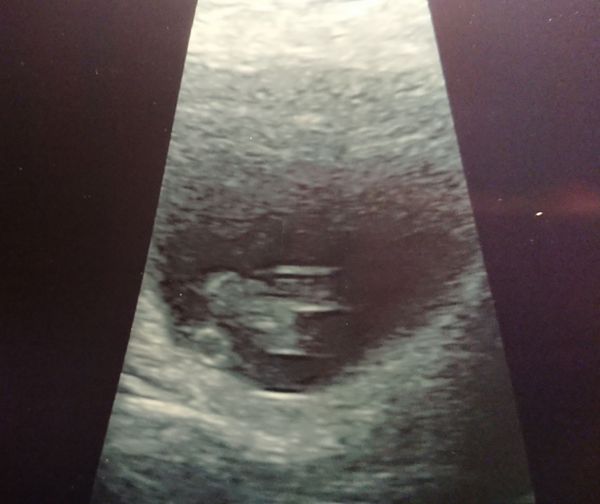

All good one very wiggly baby with a strong heartbeat! Apparently I'm also a member of the tilted uterus club which is why my cramps are so painful but she said the fact it's wiggling is really reassuring and shows it's a strong one. We may, after 5 years and 5 losses, be taking one home